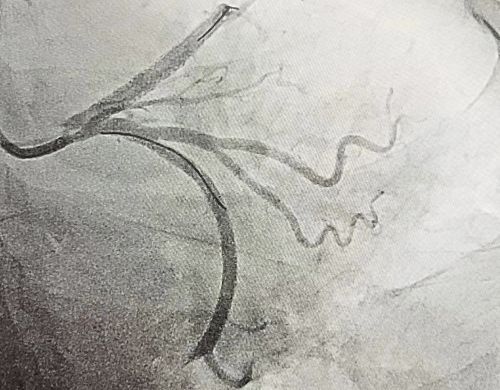

冠脉手术前